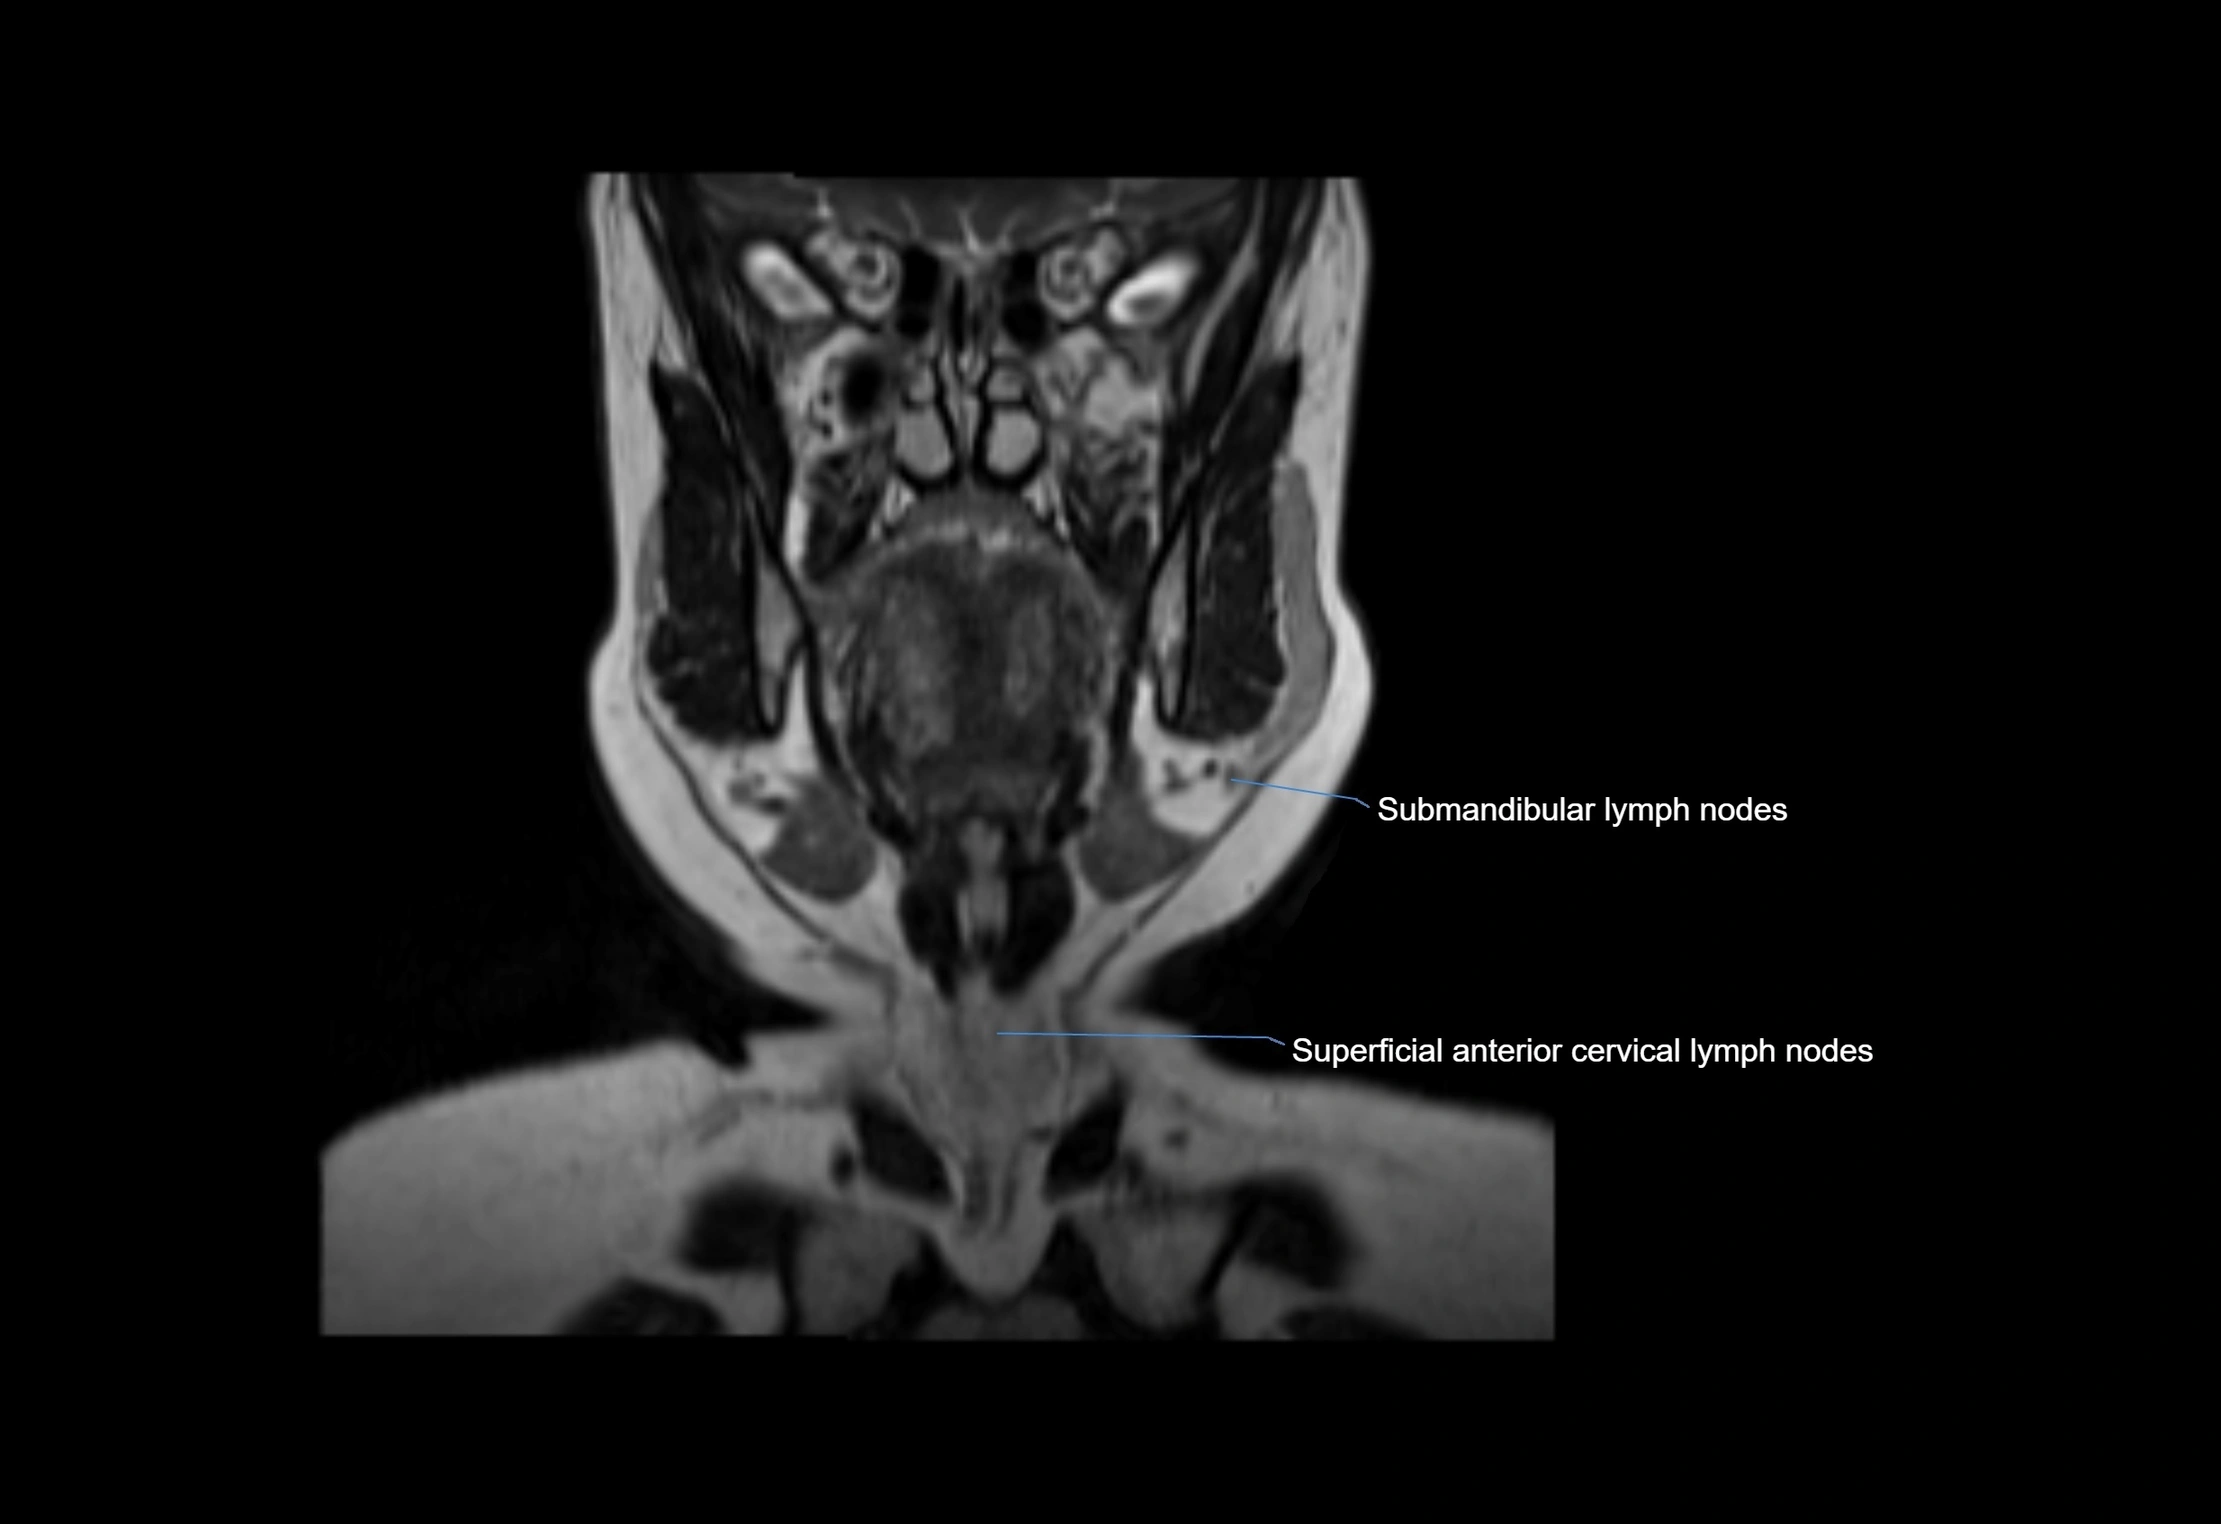

MRI Appearance

T1-weighted images:

• Normal accessory nodes appear as small, oval hypointense to intermediate signal structures within subcutaneous fat

• Surrounded by hyperintense fat, enhancing contrast for visualization

• Pathological nodes may appear enlarged or rounded, sometimes with cortical thickening

T2-weighted images:

• Nodes show intermediate signal, with surrounding fat bright

• Useful for detecting edema, inflammation, or infiltration

• Fatty hilum may appear slightly hyperintense relative to cortex

STIR (Short Tau Inversion Recovery):

• Fat suppression enhances visualization of edematous or pathological nodes

• Normal nodes appear low to intermediate signal, while inflamed or metastatic nodes appear hyperintense

• Useful for detecting subtle lymphadenopathy or early pathology

MRI images